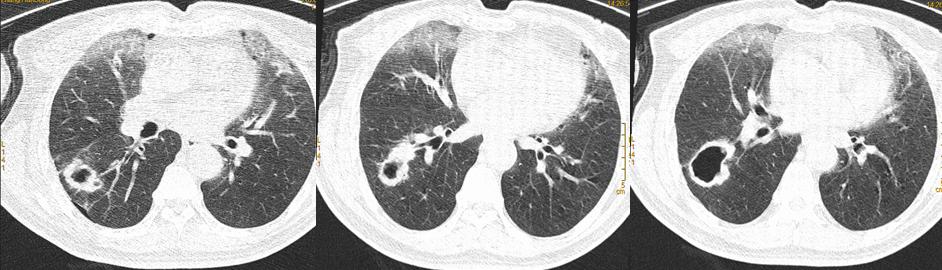

术前影像学检查(2020.7)

*CT显示右肺下叶癌性空洞性病变,纵膈无淋巴结转移。